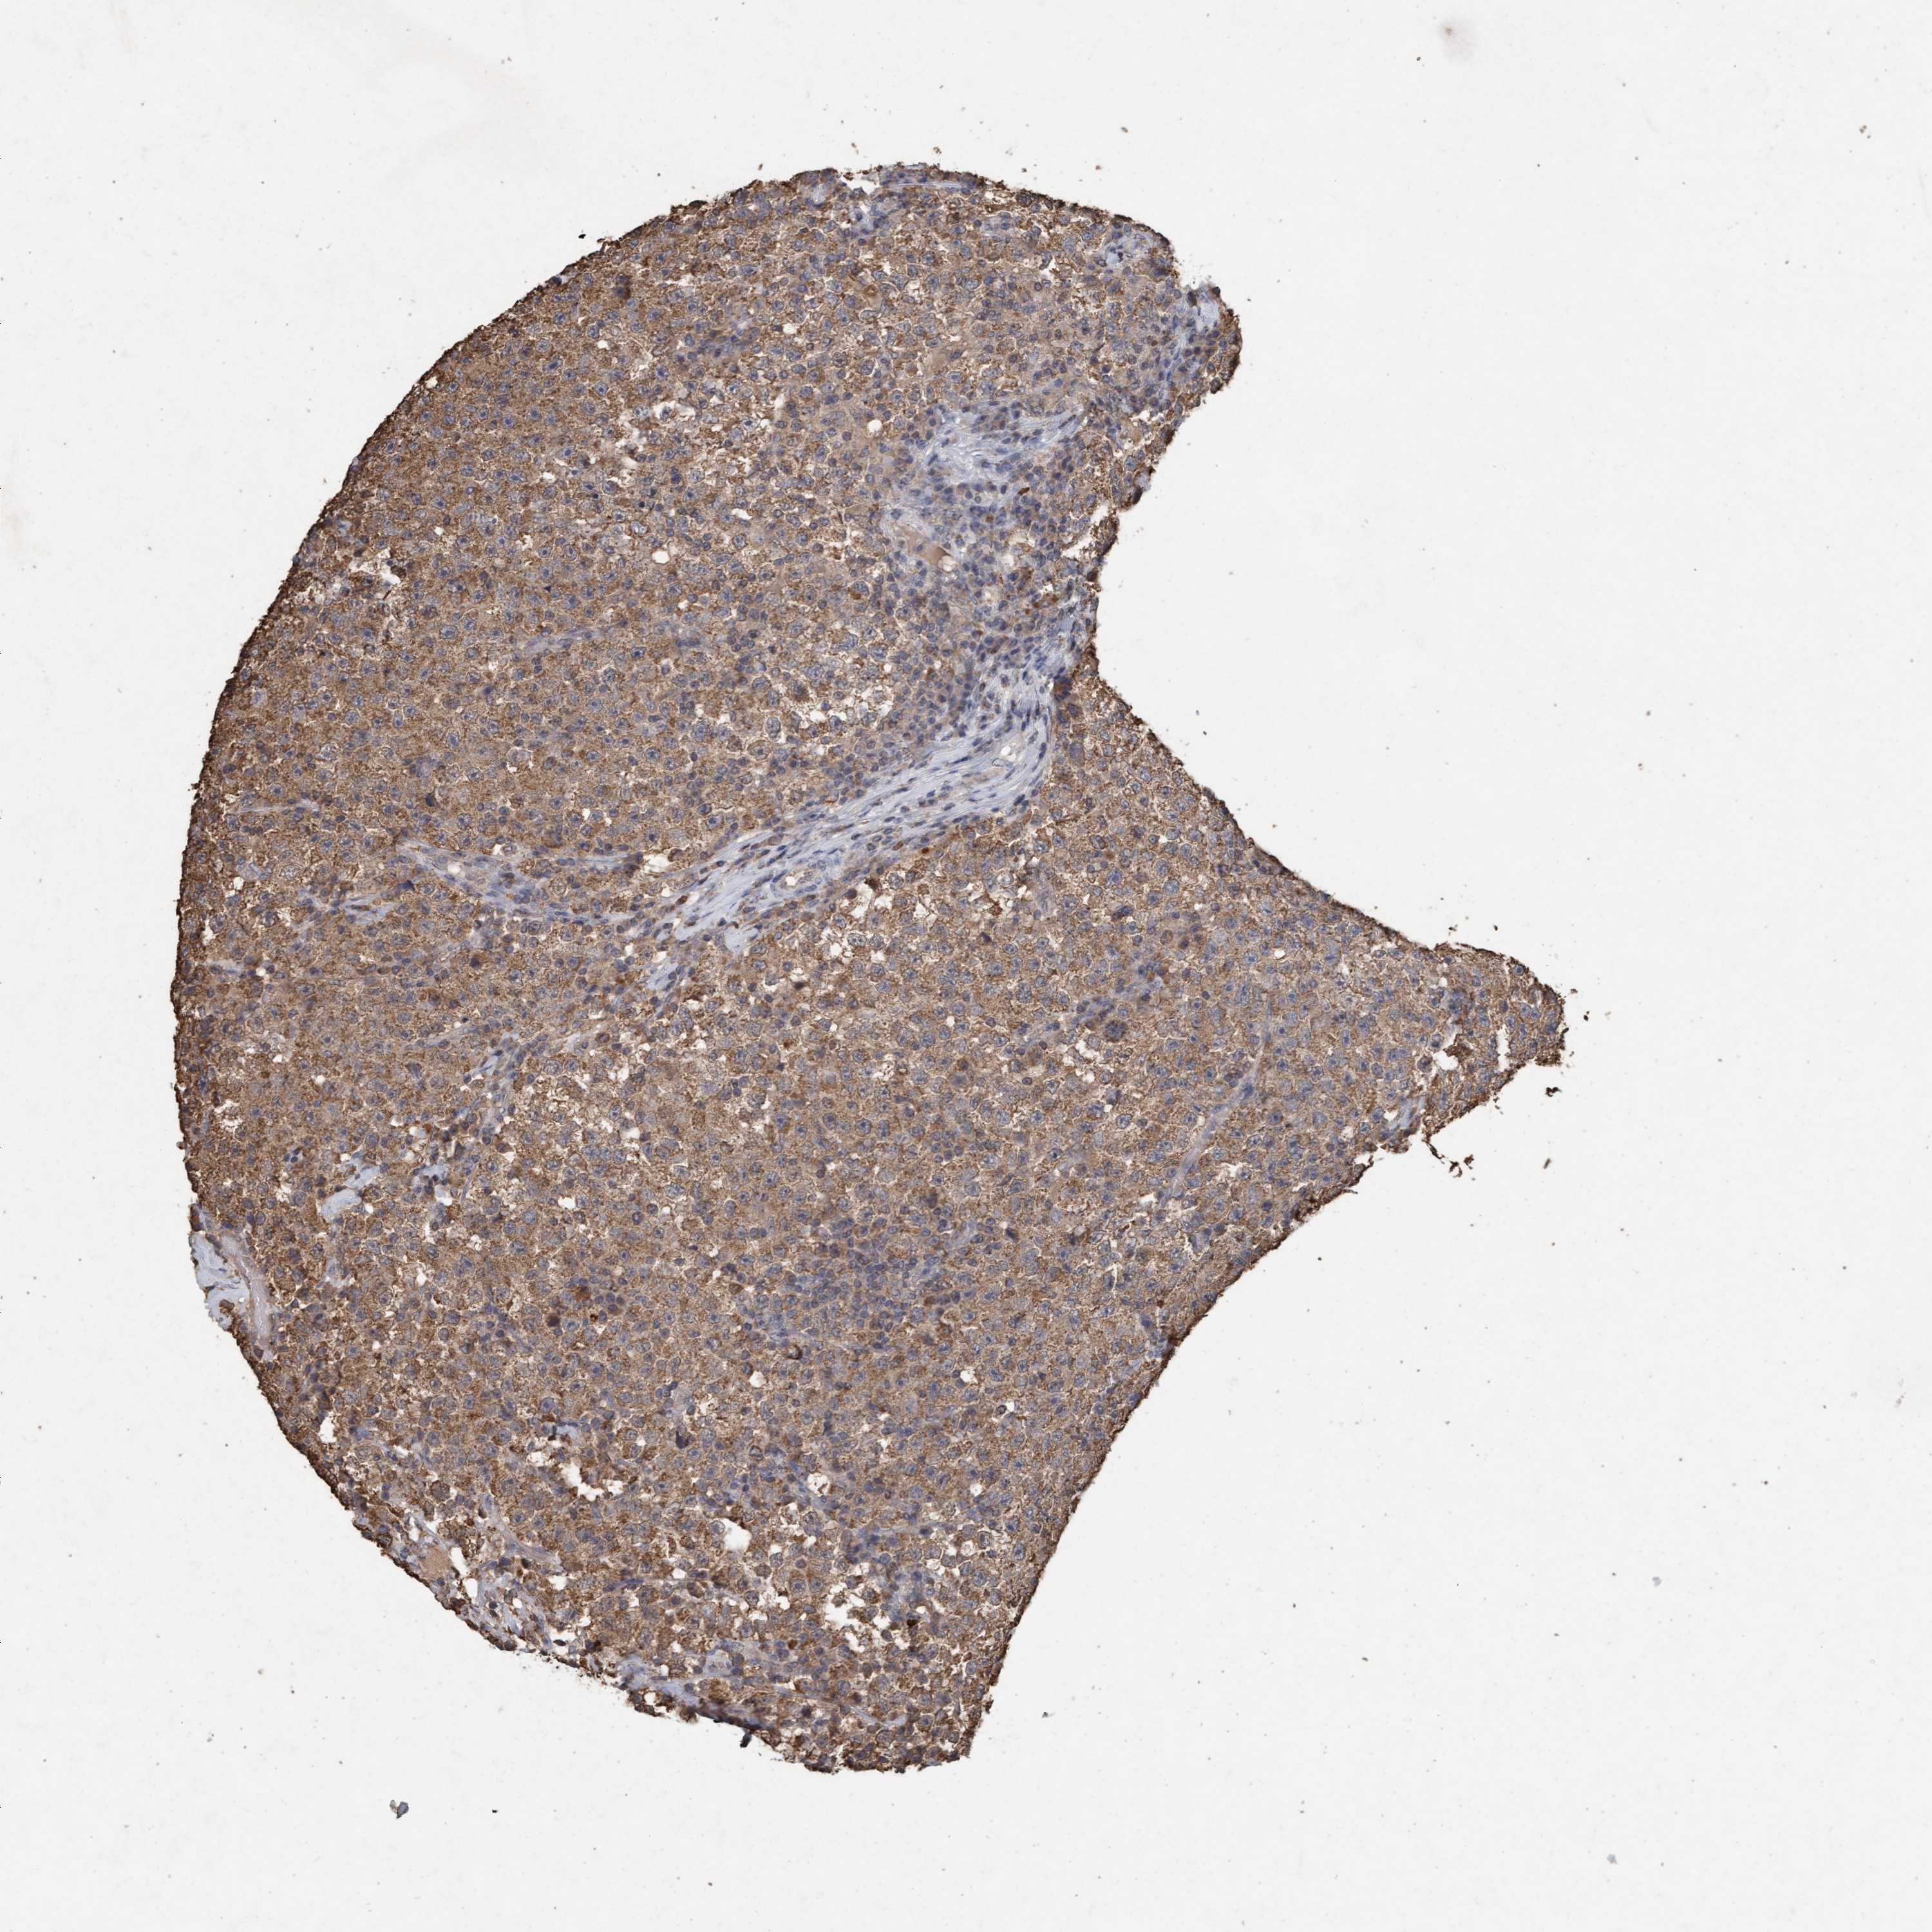

TESTIS CANCER - Protein expressioni

A mouse-over function shows sample information and annotation data. Click on an image to view it in a full screen mode. Samples can be filtered based on level of antibody staining by selecting one or several of the following categories: high, medium, low and not detected. The assay and annotation is described here.

Note that samples used for immunohistochemistry by the Human Protein Atlas do not correspond to samples in the TCGA dataset.

Antibody stainingi

Antibody staining in the annotated cell types in the current human tissue is reported as not detected, low, medium, or high, based on conventional immunohistochemistry profiling in selected tissues. This score is based on the combination of the staining intensity and fraction of stained cells.

Each image is clickable and will lead to virtual microscopy that enables deeper exploration of all samples and also displays staining intensity scores, fraction scores and subcellular localization as well as patient and tissue information for each sample.

Antibody HPA023219

Staining

High

Medium

Low

Not detected

Intensity

Strong

Moderate

Weak

Negative

Quantity

>75%

75%-25%

<25%

None

Location

Nuclear

Cytoplasmic/membranous

Cytoplasmic/membranous,nuclear

Carcinoma, Embryonal, NOS

Seminoma, NOS